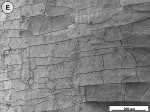

When the tooth slices with the ex vivo-grown salivary biofilm were examined under the scanning electron microscope, they were colonized by luxuriant biofilm covering the entire surface (Figure 2A, Figure 2B, Figure 2C). The biofilms appeared to be several micrometers thick. The predominant morphotypes in the biofilms were fusiform bacteria and cocci. Several regions showed co-aggregation between the two morphotypes, which is a phenomenon of mutual dependence for nutrition and growth. The salivary-derived biofilm showed characteristics typical of a naturally occurring in vivo biofilm in the mouth. The standard jet tip treatment for 3 seconds on the tooth slices with ex vivo-grown biofilm showed extensive areas of biofilm removal in comparison with the untreated control slices (Figure 2D, Figure 2E, Figure 2F). The standard jet removed 99.99% of the salivary biofilms. The orthodontic tip treatment for 3 seconds on the tooth slices appeared to clear very extensive areas of ex vivo-grown salivary biofilm (Figure 3A andFigure 3B). Biofilm removal was observed both at the crown surface and below the cementoenamel junction. The percentage of biofilm removed by the orthodontic tip was 99.84%. Observation with the naked eye indicated that treatment of in vivo biofilm with the orthodontic tip removed significant amounts of this calcified biofilm. This was evident in SEMs, which showed the presence of clearance marks (Figure 3C) caused by the bristles associated with this tip.

Comparing dental biofilm against the whole spectrum of biofilm studied by biofilm engineers, dental biofilm’s susceptibility to removal by shear forces fits into a logical pattern. Microbial biofilms have been shown to vary the cross-linking of the component polymers of their matrices to develop a tensile strength appropriate for their retention on surfaces in the ecosystem in which they operate. Various degrees of mineralization of biofilms make them much more resistant to removal by shear forces. In the oral ecosystem, mineralization takes the form of calcification, and the deeper layers of the biofilm used in this study were, in fact, calcified to the extent that they had tensile strengths approaching that of the enamel of the tooth. For this reason, the authors distinguished between the removal of less calcified ex vivo salivary biofilm and the removal of calcified biofilm that had formed over a long period on the patient’s teeth in vivo.